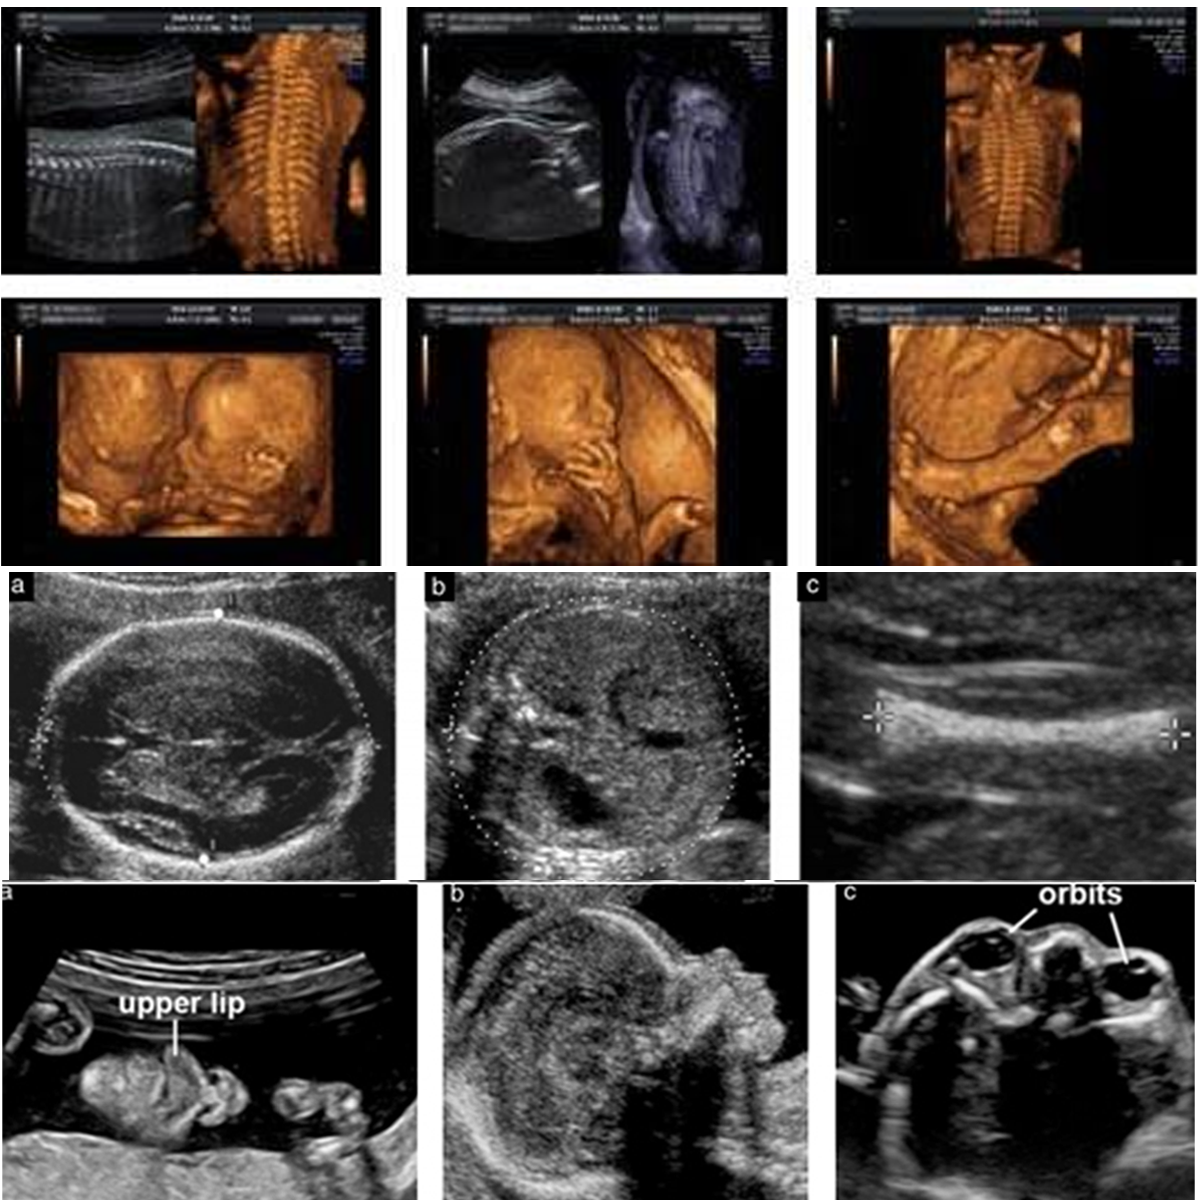

IV. Anomaly Scan / Level II (Done between 20-24 weeks):

Anomaly scan is done at 18-20 weeks of gestation to rule out major structural problems. Fetal growth, amniotic fluid are also checked at the same time. Some patients may need a review scan in case views are not clear due to maternal obesity, previous maternal surgery or at times due to fetal position. Indian MTP law doesn’t allow termination beyond 20 weeks even in case of major malformations and hence it is recommended to do anomaly scan before 20 weeks.